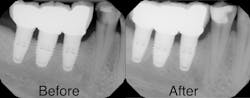

Upon clinical and radiographic examination, it was determined that the patient had a combination of caries, inflamed gingiva from desiccation, and loss of vertical dimension (figure 4). Xerostomia and insufficient home care were implicated in the patient’s elevated caries rate, as well as the presence of implants leading to implant-induced caries.

After the first phase consisting of caries control and periodontal treatment, the patient received soft- and hard-tissue crown lengthening by laser (figure 5). After an eight-week healing period, full-mouth cosmetic restorations were placed, which included full- and three-quarter-coverage e.max crowns and zirconia bridges (figures 6–7).